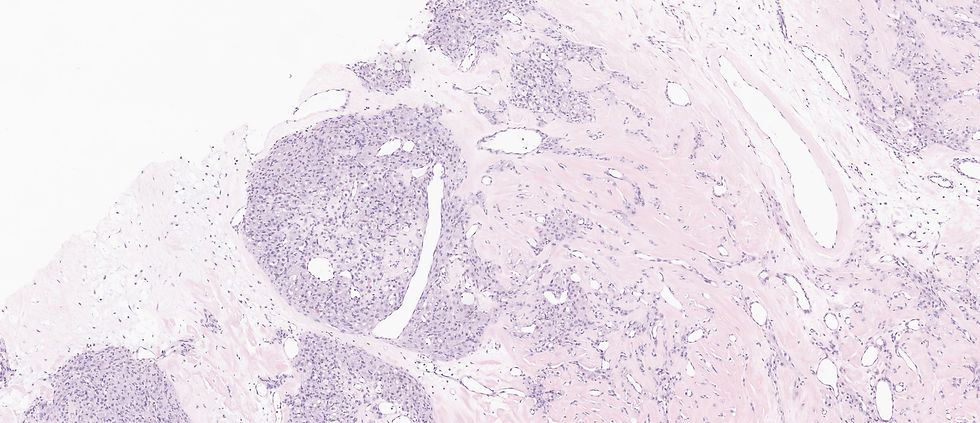

The correct answer is E. This is a classic case of sclerosing stromal tumor: 1) alternating cellularity 2) pseudo-lobular appearance 3) thin walled dilated staghorn vessels. The pseudolobules in a myxoid, edematous, or collagenous stroma is characteristic.